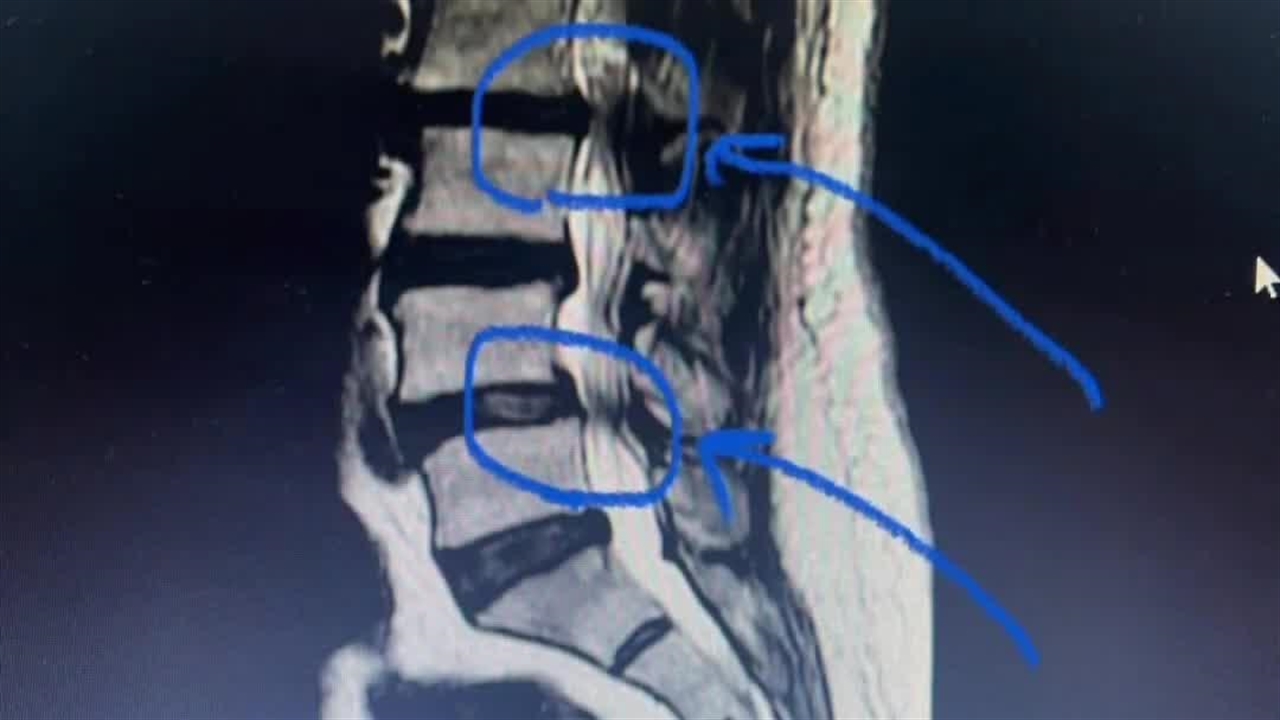

درمان قطعی دیسک کمر

جراح مغز و اعصاب و ستون فقرات